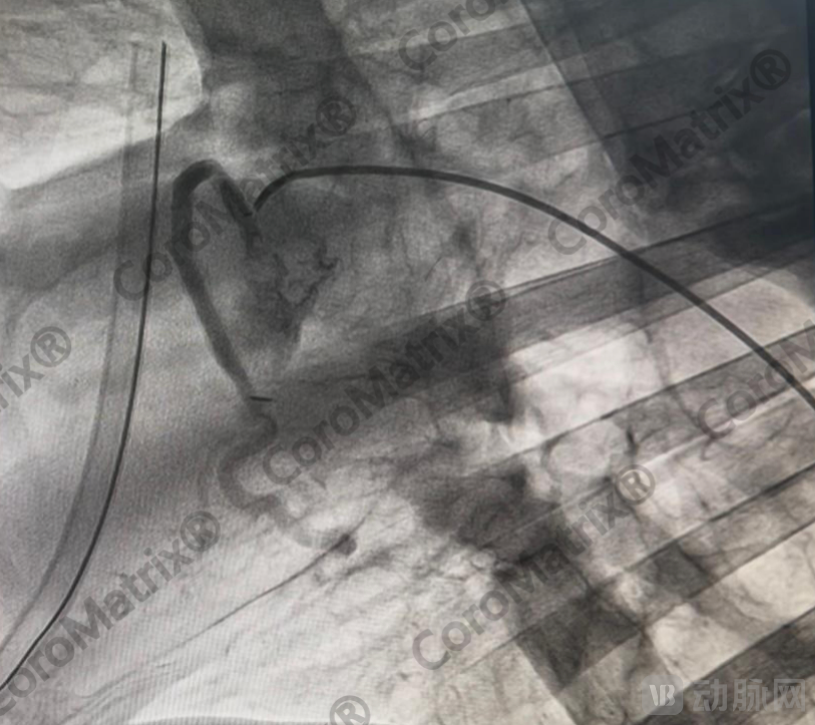

最近Xeltis、Vascudyne分别公布了部分冠脉搭桥临床试验结果,Medical 21本月启动了欧洲临床试验,Humacyte计划2026年Q1-Q2启动临床试验。海迈医疗与国际同行同步,已经积累临床前大动物实验长期随访结果,预计2026—2027年启动3.5mm内径CoroMatrix蔻迈通®️生物型人工血管冠脉搭桥临床试验,而依据FDA指导原则,过去40年以来只要含高分子材料的传统人工血管严禁用于冠脉搭桥。

CoroMatrix蔻迈通®️人工血管用于羊冠脉搭桥术后DSA随访结果